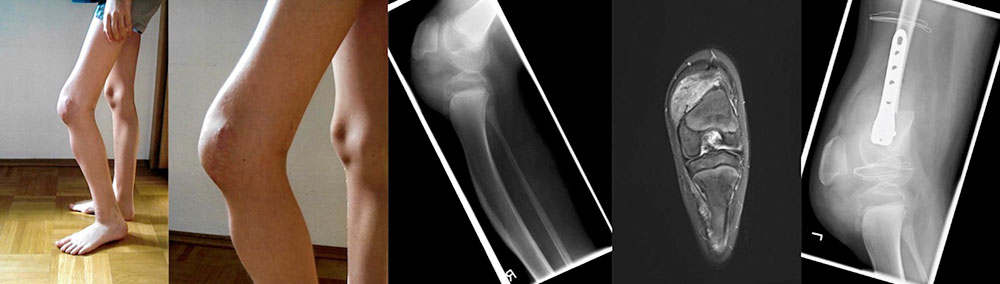

12-year-old patient with PTEN hamartoma of soft tissue in the area of the thigh directly above the left patella. As a result of pain caused by mechanical pressure during knee extension, a flexion posture was always adopted. Additionally there was leg length discrepancy with an excess length of approx. 3 cm of the left leg. The detailed picture shows the maximum possible active extension of the left knee. The X-ray shows additional dysplasia of the tibia. The vascular tumor (PTEN hamartoma) is located in the area of the distal thigh. Because the PTEN hamartoma is located mainly medial to the distal femur (T2-weighted MRI), a conversion osteotomy of the femur was planned via a lateral approach. The goal was to correct the knee flexion contracture with a single operation. Treatment of the vascular tumor was not the goal of therapy. As the patient had an excess length of more than 3 cm on the affected side, it was decided to perform the operation as a “closed-wedge” osteotomy and to correct the leg length discrepancy as well. Lateral X-ray image after the operation. The patient can now fully extend the left knee. Plaster or other immobilization is no longer necessary thanks to the use of a stable-angle implant. Thus, the patient can use his compression garments again and the duration of anticoagulation can be shortened.

Note: 1. The two visible threads are the radiographic strips of the dressing on the surgical wound.

Note: 2. The clear caliber jump above and below the osteotomy results from the removal of the 3 cm measuring wedge to correct for the leg length.